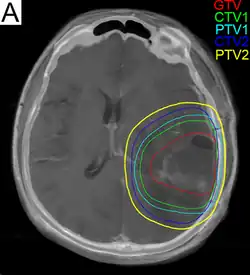

.png)

Subsequent to surgery, radiotherapy becomes the mainstay of treatment for people with glioblastoma. It is typically performed along with giving temozolomide.[10] A pivotal clinical trial carried out in the early 1970s showed that among 303 GBM patients randomized to radiation or best medical therapy, those who received radiation had a median survival more than double those who did not.[77] Subsequent clinical research has attempted to build on the backbone of surgery followed by radiation. Whole-brain radiotherapy does not improve when compared to the more precise and targeted three-dimensional conformal radiotherapy.[78] A total radiation dose of 60–65 Gy has been found to be optimal for treatment.[79]